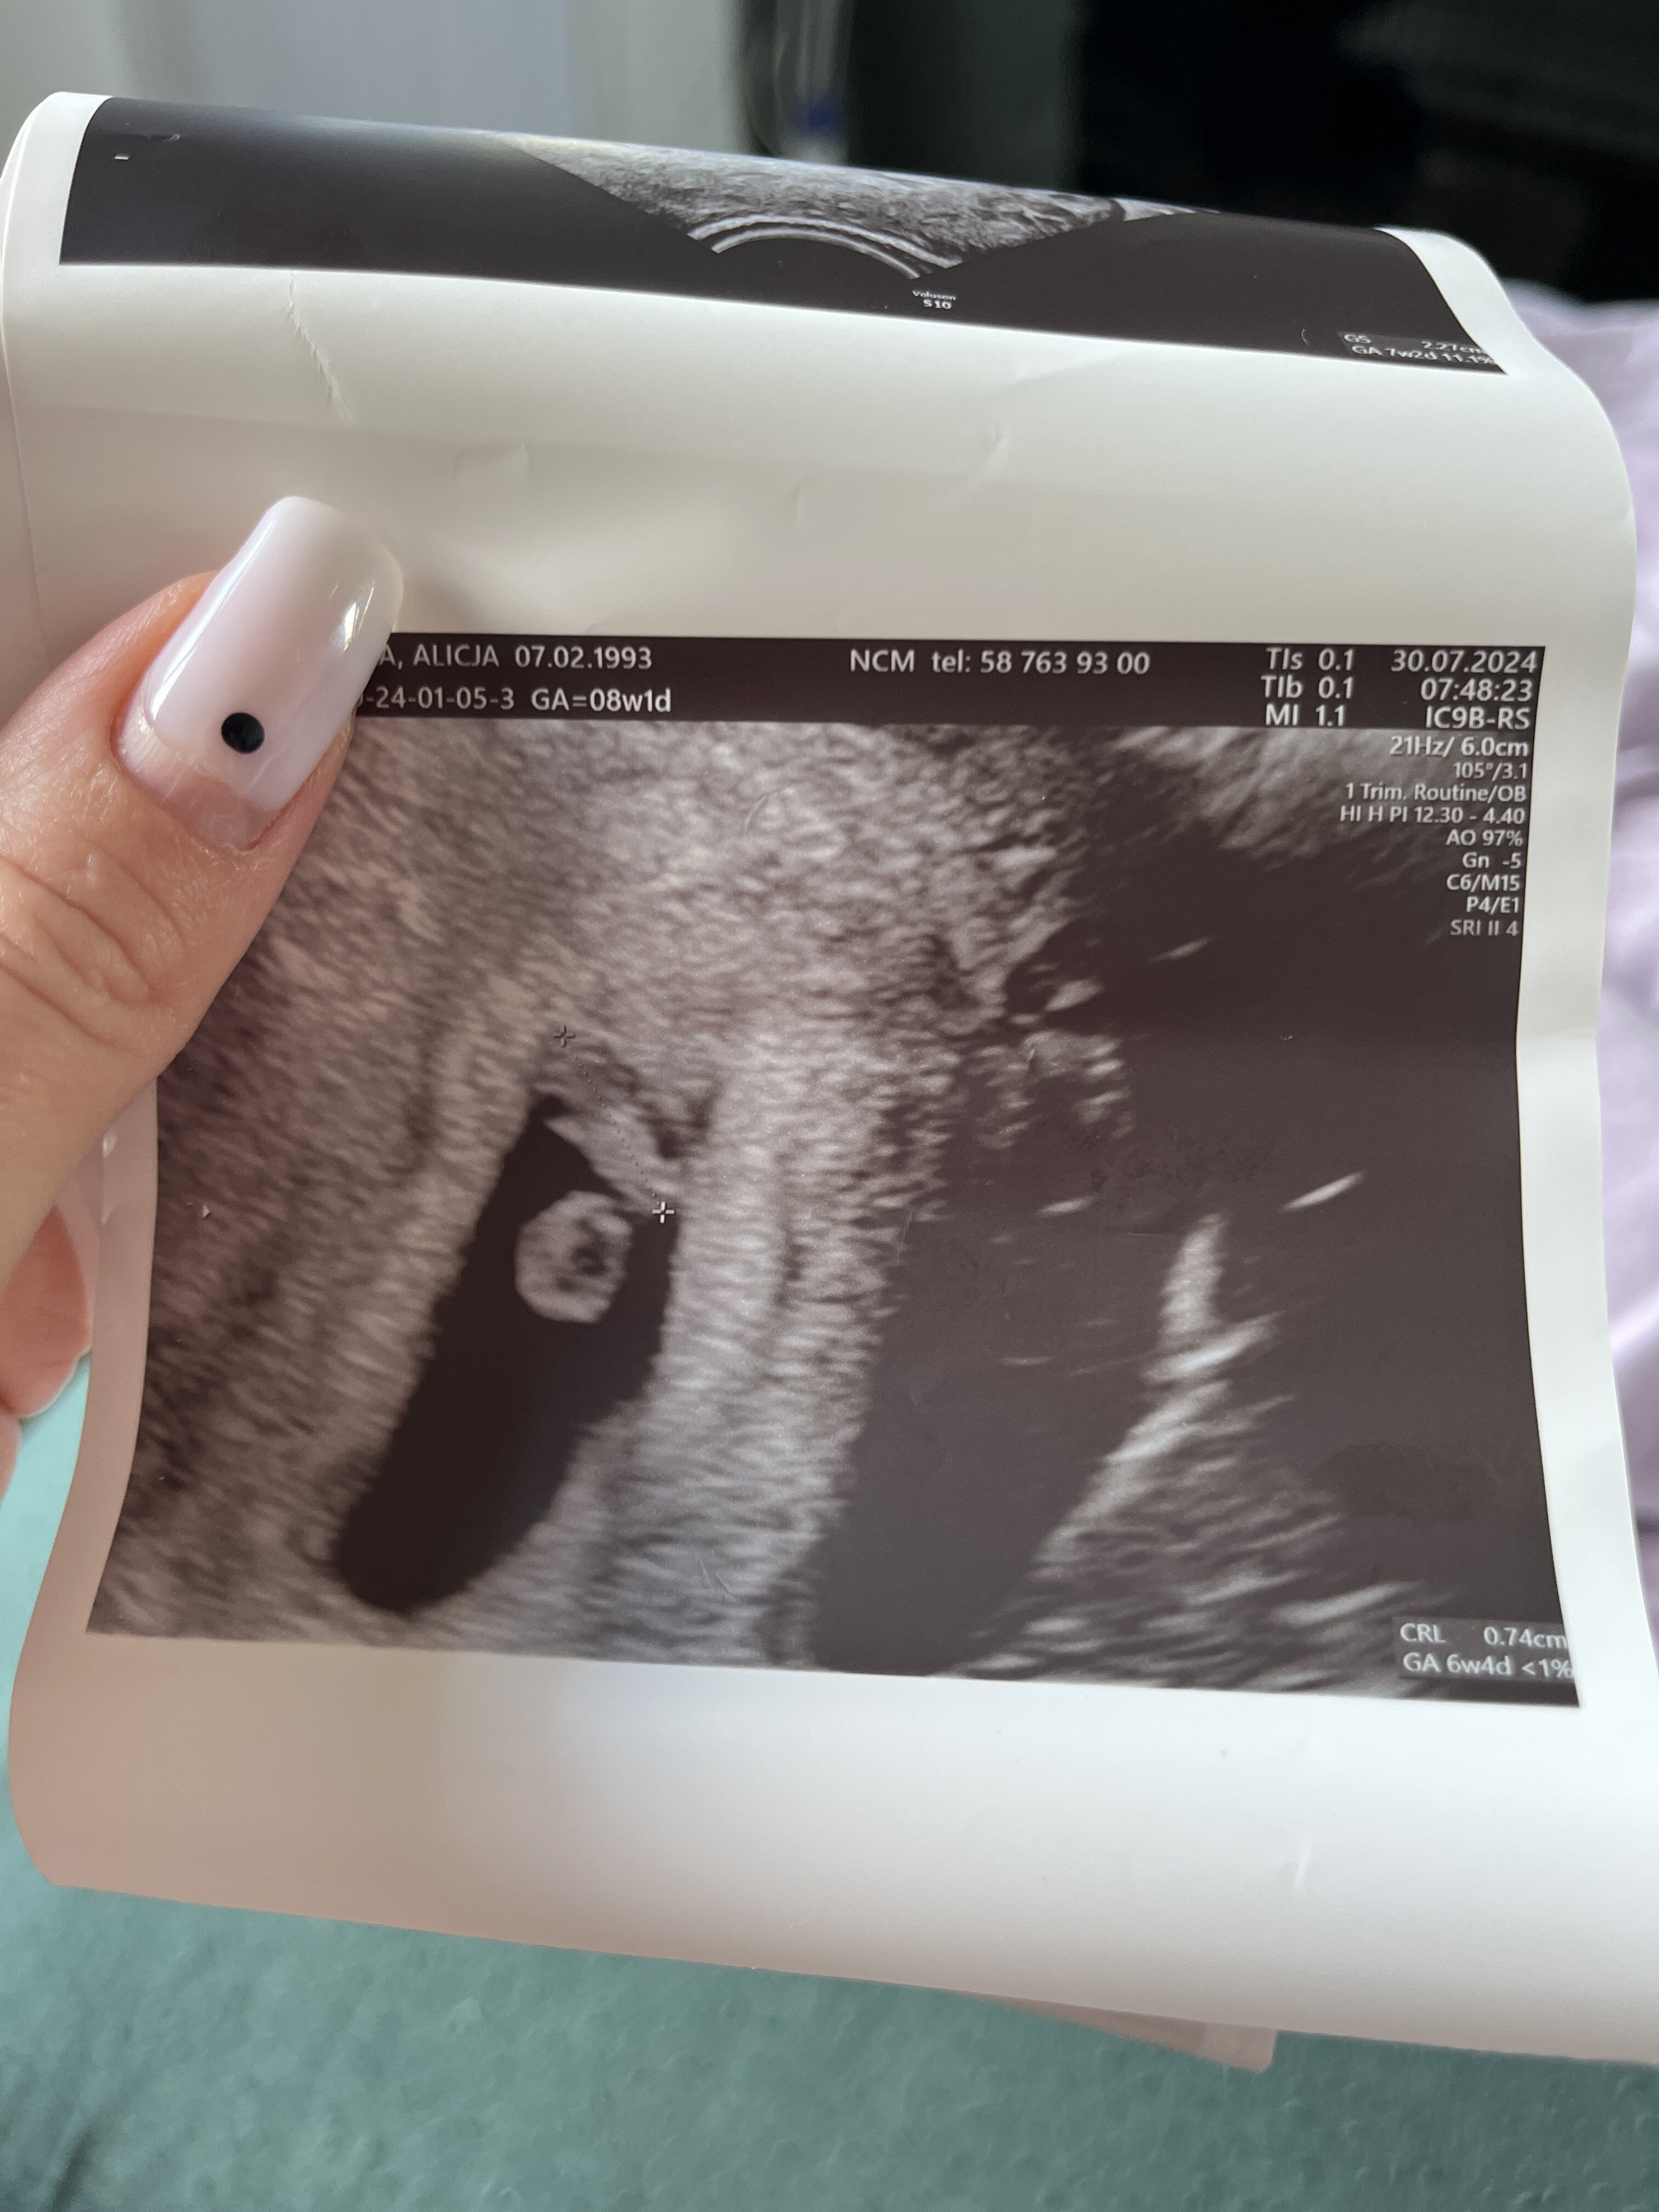

Jestem po wizycie , dalej nie wierzę wczorajsza beta za mały przyrost i szłam na wizytę z nastawieniem że będzie łyżeczkowanie , a tu dzidziuś z bijącym serduszkiem

Z rozmiarów 6 tydzień i 4 dni , ale mam się posługiwać terminem 7 tydzień i 2 dzień bo z miesiączki wychodzi 8+1

Ale wychodzi na ciążę młodsza 10 dni .

Termin na 16 marca